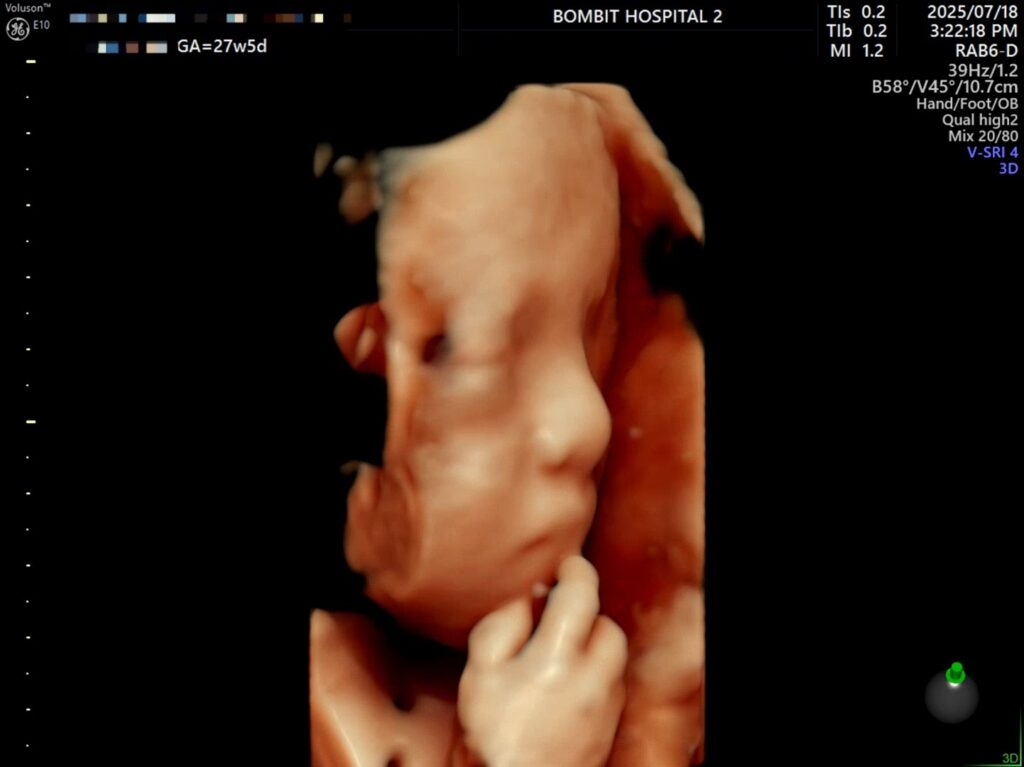

초코우유도 못 먹는 몸인지라, 초음파실 샘이 권유한대로 물을 마시고 로비를 한 3바퀴정도 힘차게 걷고 나서 다시 초음파를 봤다. 단비가 여전히 엎드려있길래 선생님이 배의 특정 부분을 두드리셨는데(단비 미안).. 단비가 움직였다!

그렇게 다행스럽게도 단비 얼굴을 볼 수 있게 되었다.

– 통통한 손가락

입초로 본 단비 얼굴은 정말 너무너무 귀여웠다!! 보면서 코가 복코같이 눌려있다고 생각했는데,, 선생님은 아기 콧대가 높다고 했다. 엄마를 닮아서 그런 듯(?)ㅋㅋㅋ